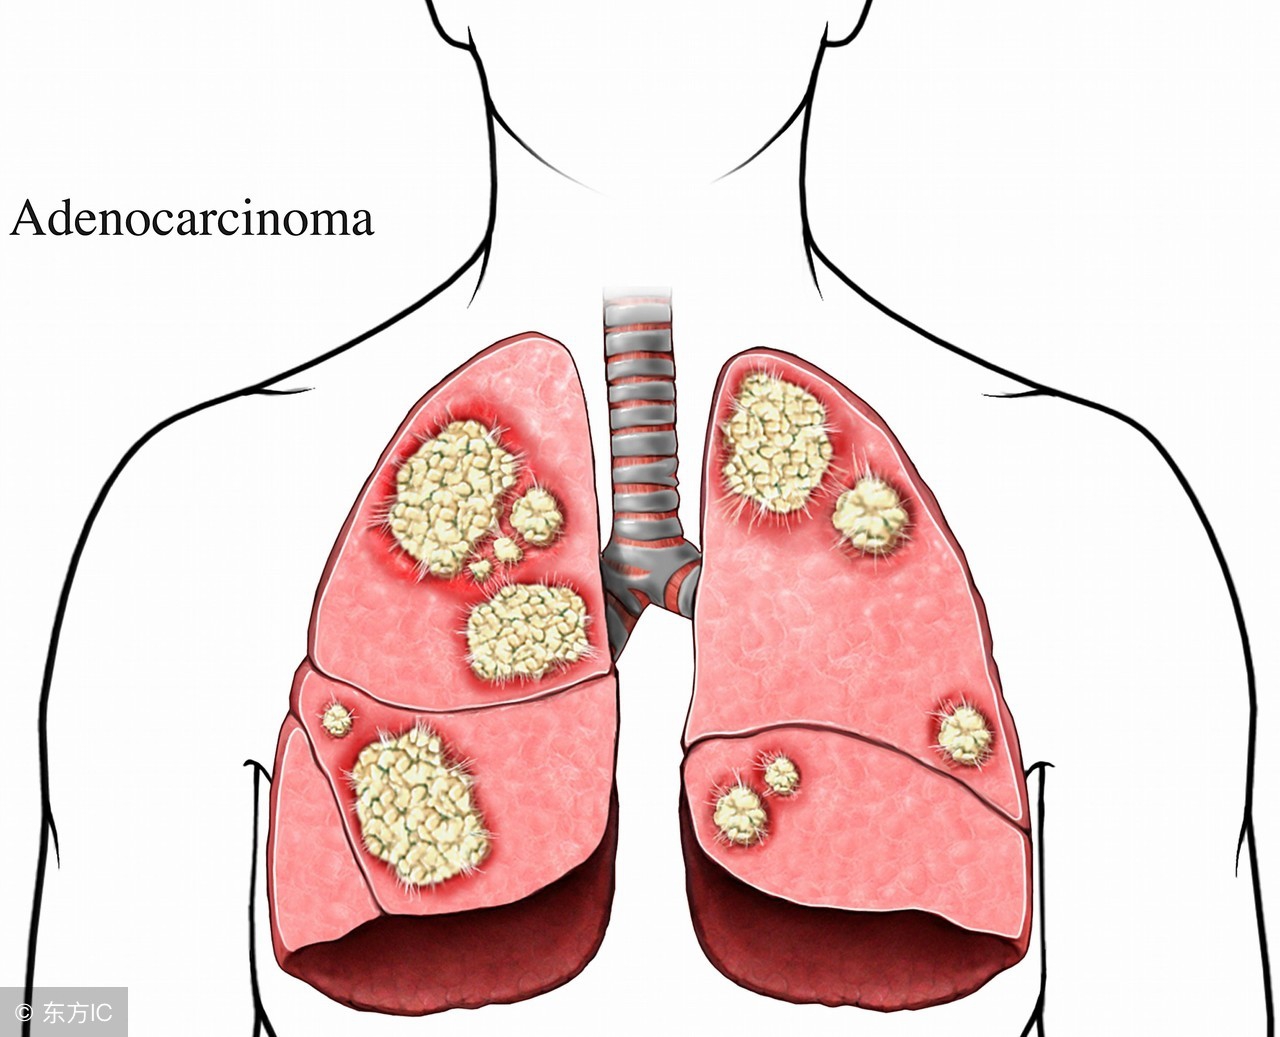

一般引起肺纹理增多的原因很多,既可以是生理性的,也可能是病理性的,常引起本症状的疾病有慢性支气管炎、支气管扩张、风心病、先心病、尘肺、癌性淋巴管炎等呼吸和心律增快、肺部罗音、肺动脉瓣第二心音亢进。胸片呈现肺部斑片状或楔状阴影,盘状肺不张一侧膈肌抬高,肺动脉增粗和局限性肺纹理减少血气分析PaO210、64kpa,肺泡氧分压与动脉血氧分压差增大;死腔/潮气量比值(VD/VT)40%;血乳酸脱氢酶450U,谷草转氨酶(AST)和肌酸磷酸激酶(CPK)正常血红素增高